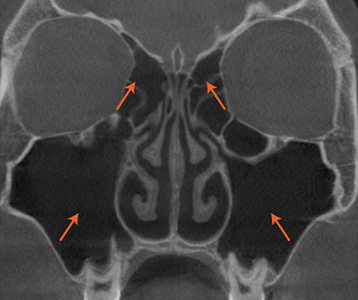

• 재수술 전

• 재수술 후

1차 수술 재발 원인 정확히 분석

완성도 높은 재수술을 위해

CT, 문진, 내시경, 후각, 음향,

통기도 검사 진행.

현재 상태를 정확히 분석합니다.